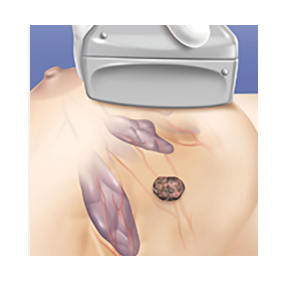

The cycle is activated and an iceball forms around the tumor. The freezing temperatures destroy the tumor tissue

Freeze and thaw cycles are used sequentially to destroy the tumour

This creates a large ball of ice that engulfs the tumor. By alternating freeze and thaw cycles, the cells in the tumor are destroyed. By the end of the procedure there should be no viable cancer cells left. The progress of ice ball development is closely monitored throughout the procedure to ensure safety.